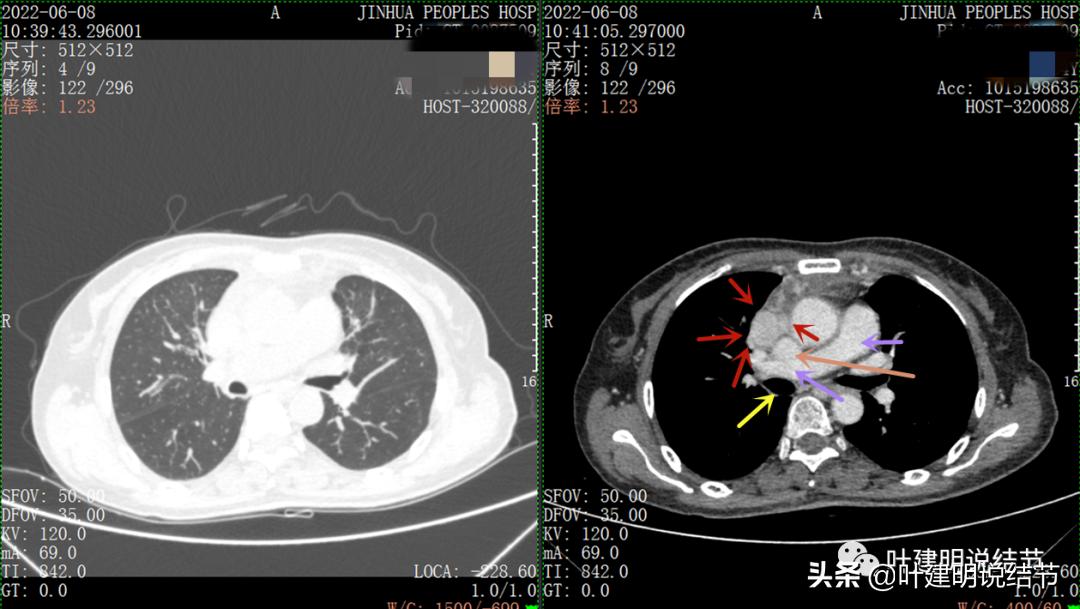

以下图片左侧是肺窗,右侧是纵隔窗。红色箭头示病灶,桔色箭头示无名静脉,黄色箭头示支气管,砖色箭头示上腔静脉,蓝色箭头示主动脉,紫色箭头示肺动脉。

病灶最大横断面水平,在冠状位上显示病灶多个中心似的,从上到下纵隔都有

病灶之间似不相连的,矢状位上见从上到下延续的

病灶占据前纵隔从上到下全程,多中心,密度不均,对心脏与大血管有压迫,没有明显侵犯

病灶表面不平,中间有坏死

特别显示与无名静脉的关系

上图示最大横断位达5厘米